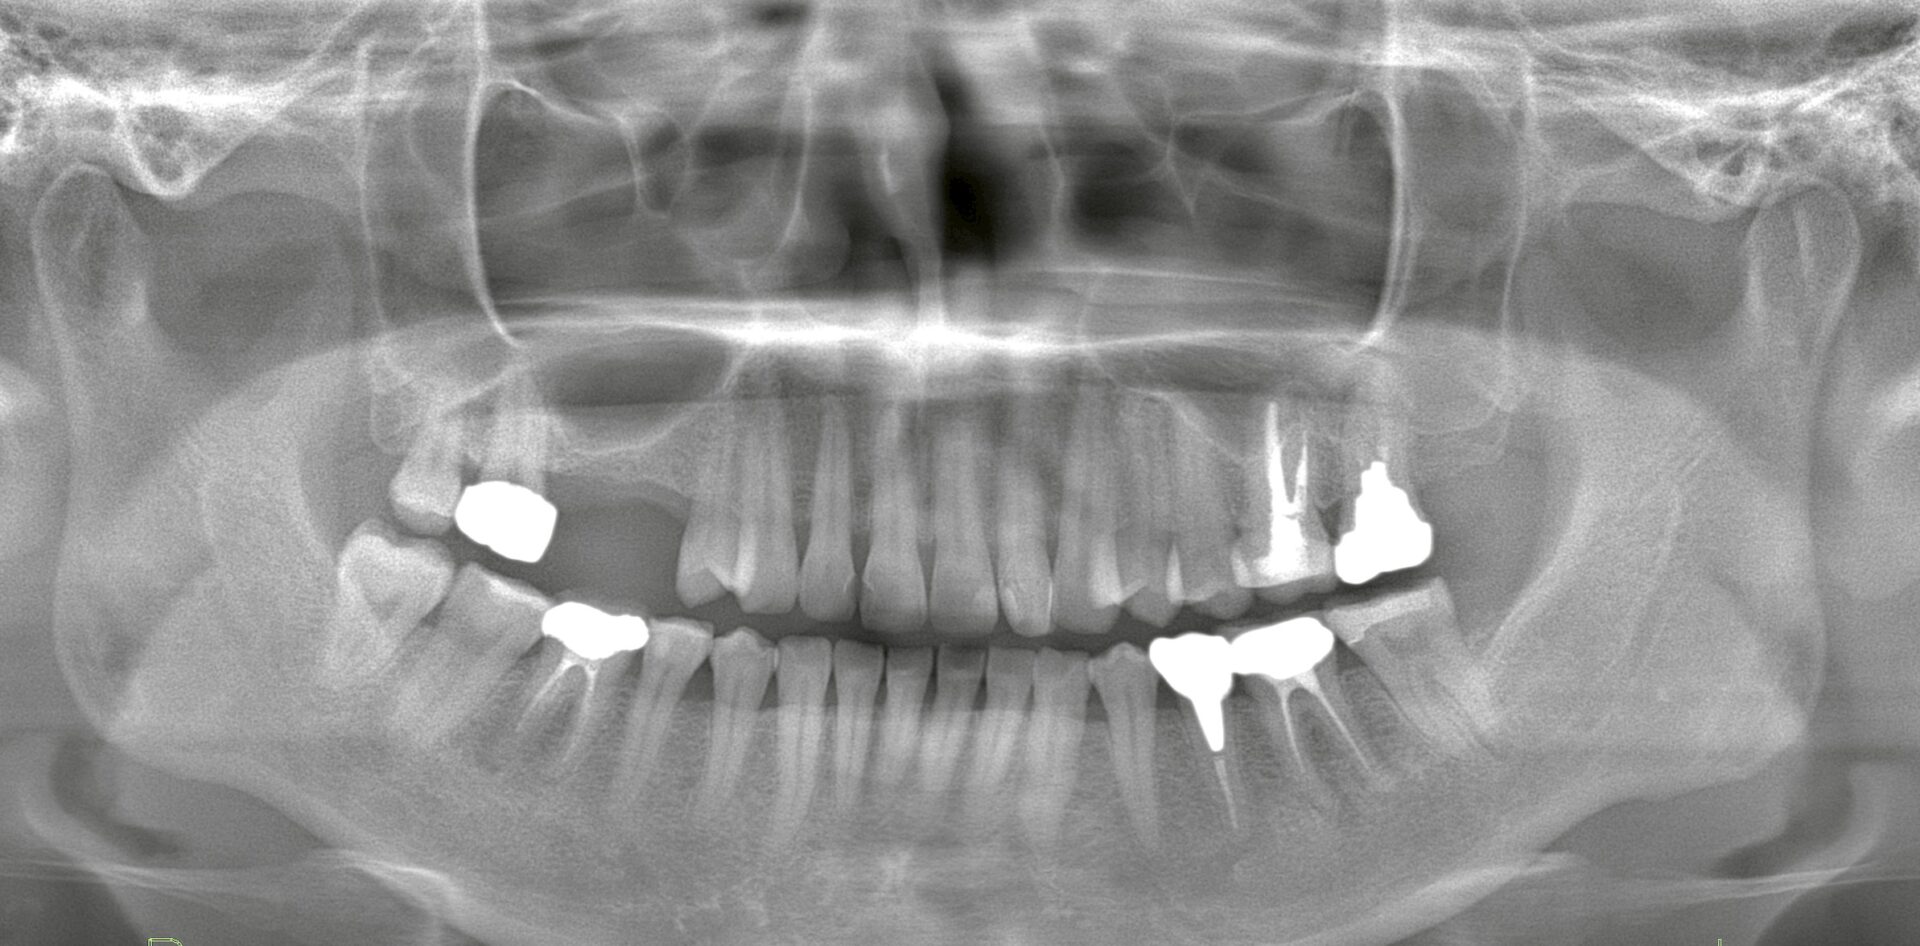

むしろ、「虫歯がないから歯科医院に行く理由がなかった」という空白の数年間が、歯周病原細菌に「無菌室ならぬ増殖室」を与えてしまい、気づいた時には骨が溶けている……というケースが後を絶ちません。

歯周病は、一度失った付着(歯を支える組織)を完全に元に戻すことが極めて難しい疾患です。また「発症後の治療」より「発症前の予防」の方が、患者様にとっての時間的・経済的・身体的コストにおいて圧倒的に効果が高いのです。